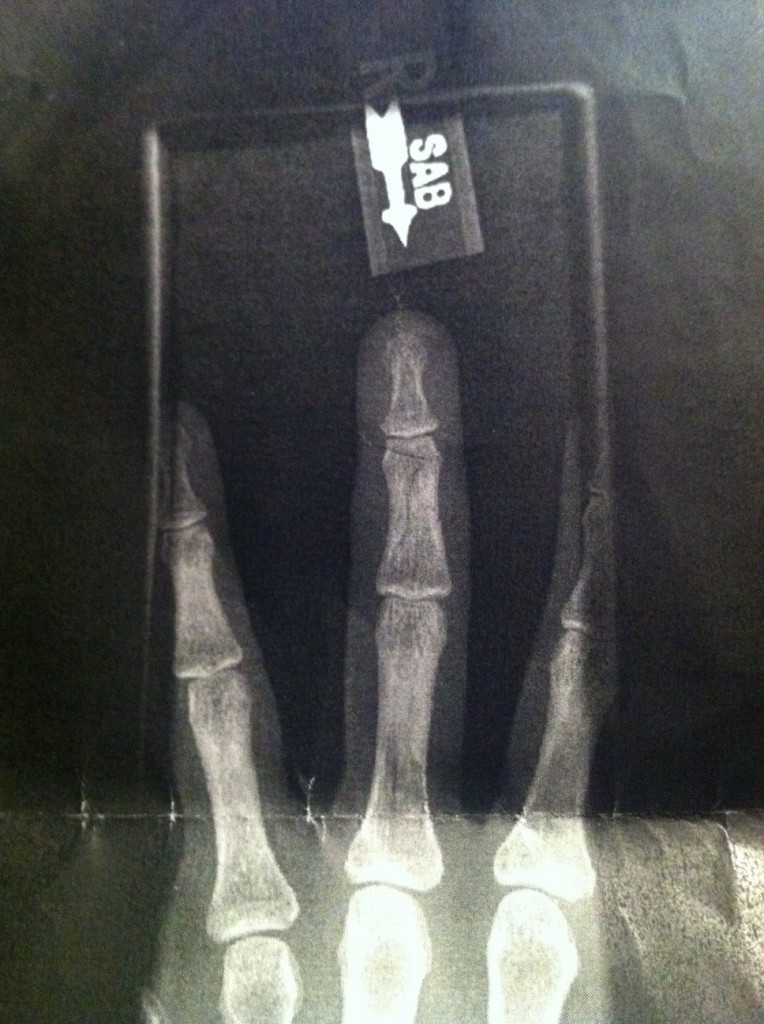

Monday after the AM feeding, I spent the majority of the day at the emergency clinic getting xrays after my finger got caught in Serenade’s lead rope, leading to this…

for those who are interested, I fractured my middle phalanx… sigh… and owwww…